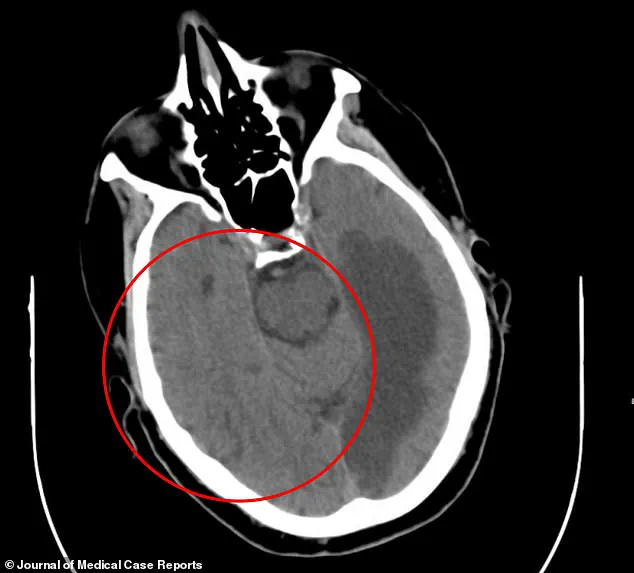

A CT scan revealed the grim truth: severe brain damage from a stroke in the left temporal and occipital lobes, areas critical for language, vision, and motion interpretation.

The damage extended into the corpus callosum, the neural bridge connecting the brain’s hemispheres.

This structure, vital for coordinating movement and cognition, was now fractured, leaving the man’s body in disarray.

A CT scan of his brain showed a disturbing fusion of gray and white matter, a sign of tissue damage that could explain the neurological dysfunction.